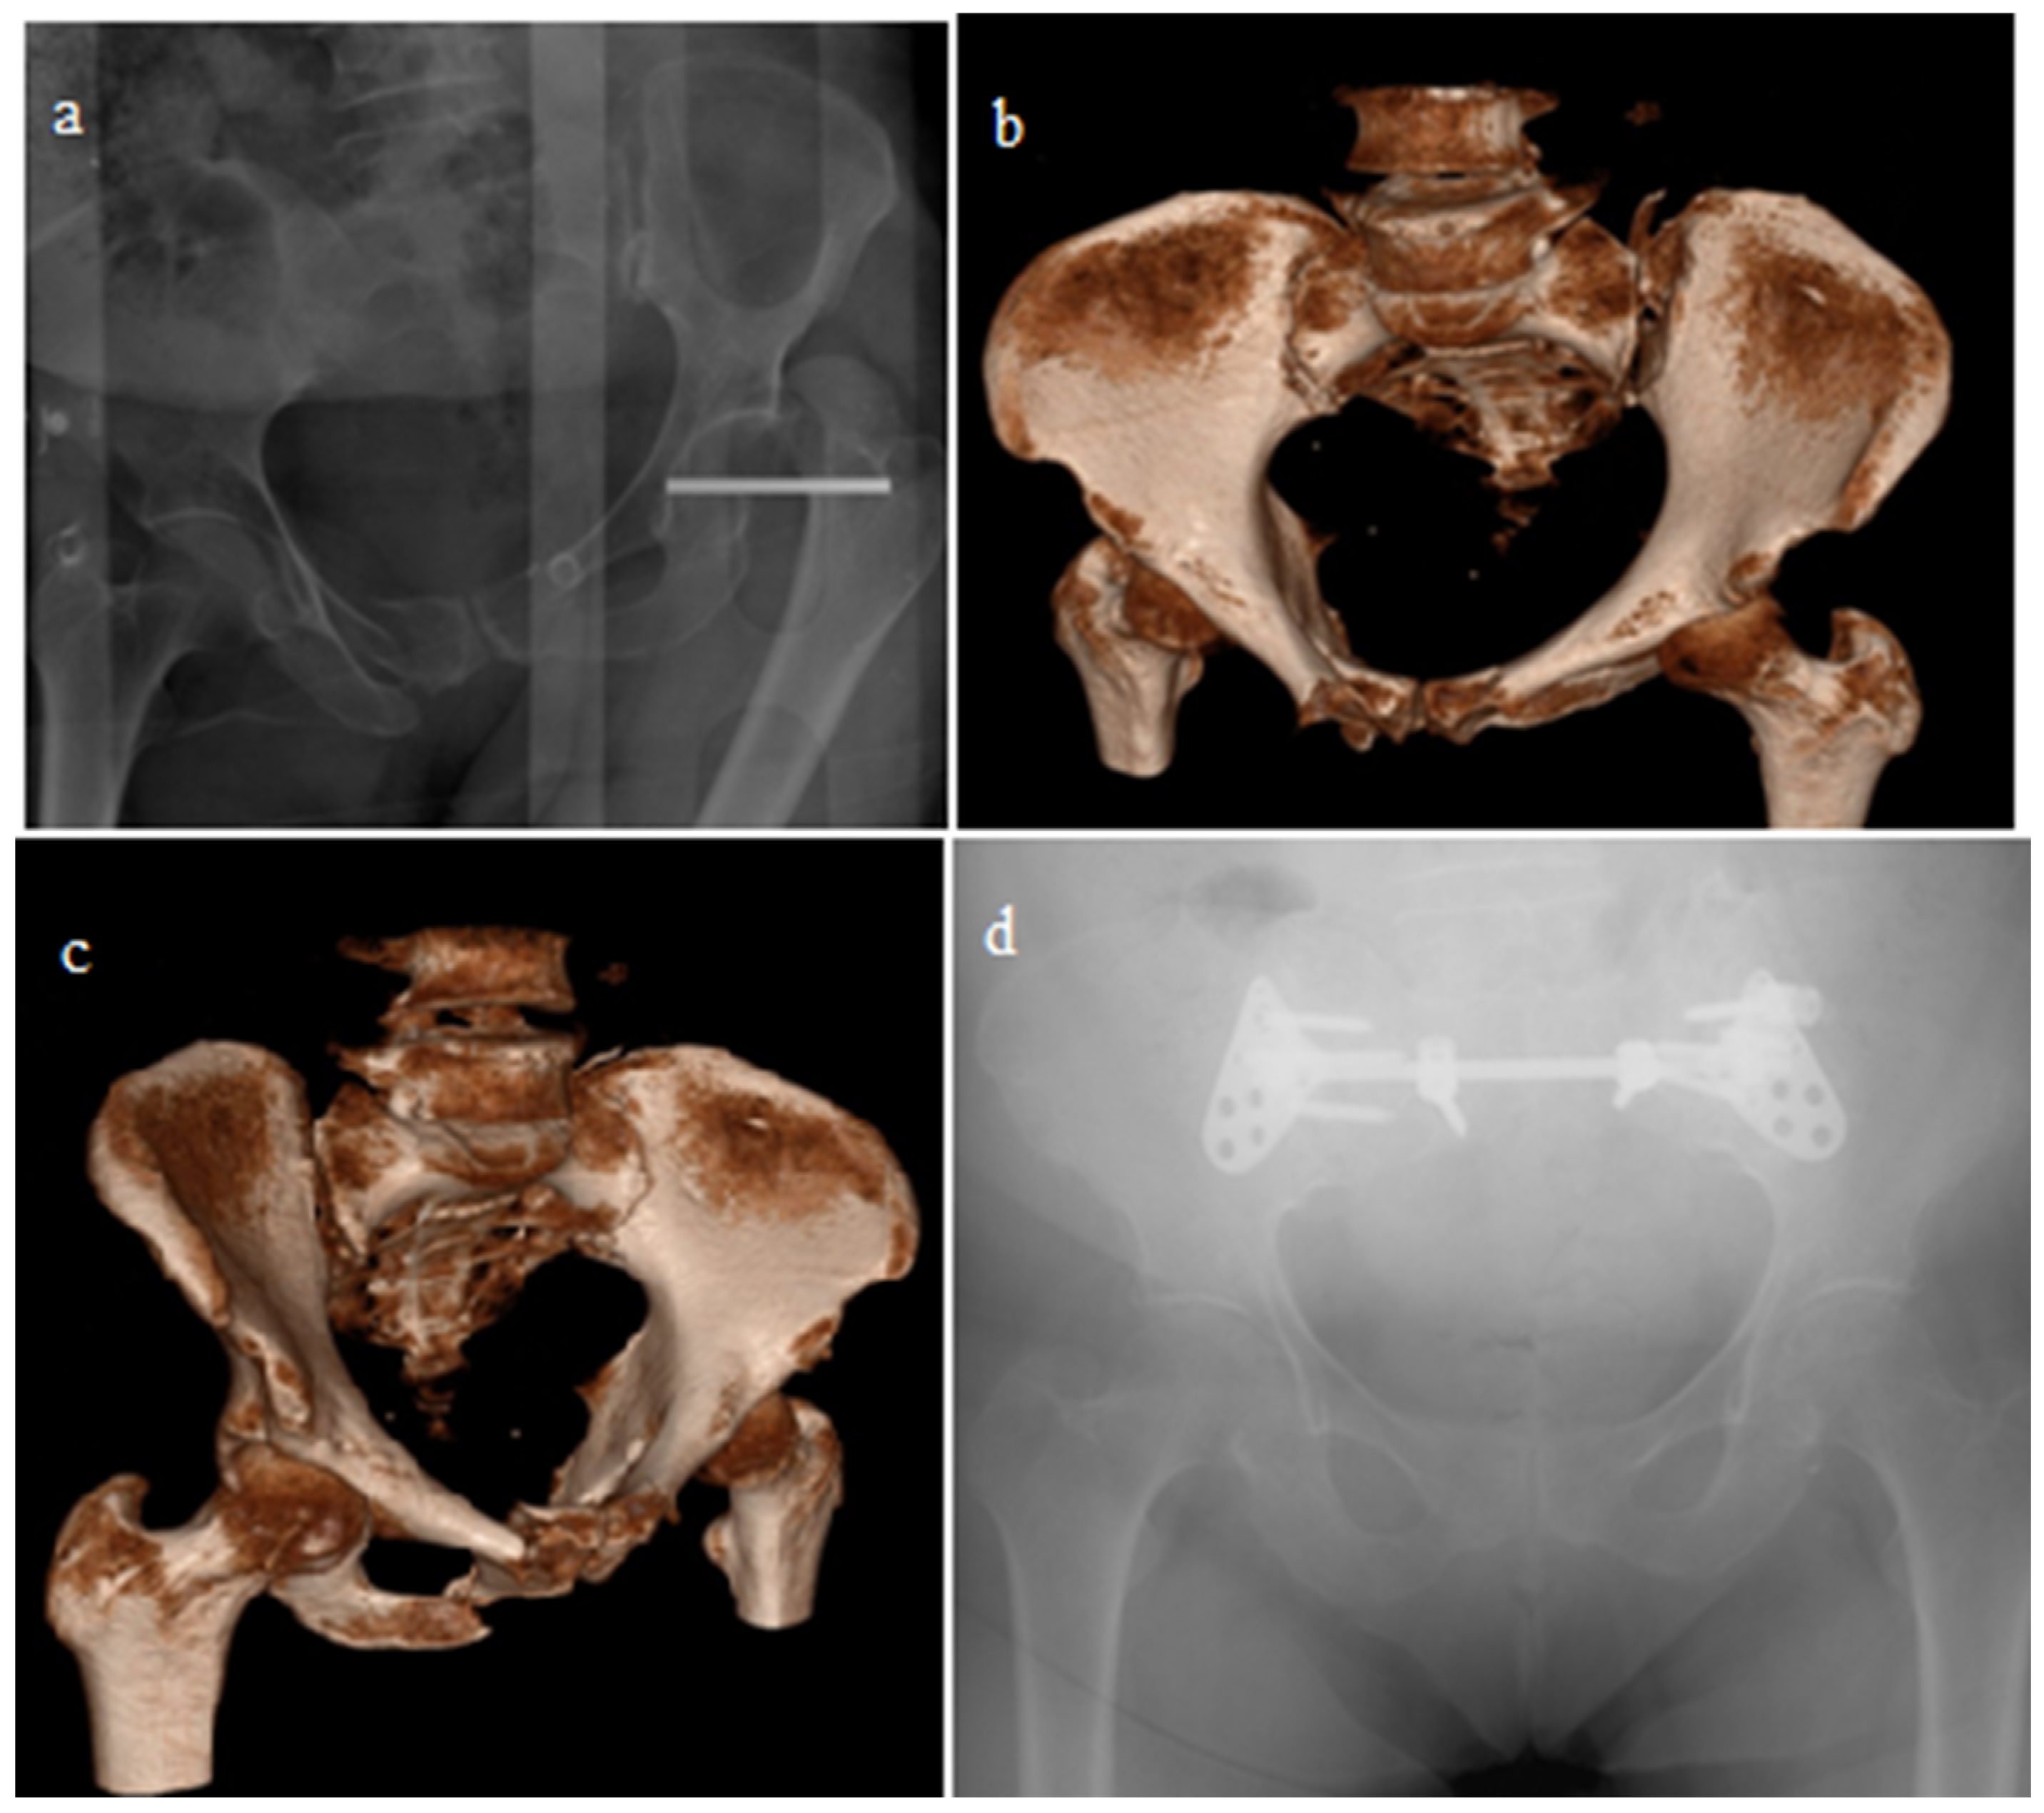

| Closed reduction + ISS | 59 | 48.7 |

| Open reduction + Anterior PS | 36 | 29.75 |

| Open reduction + Posterior PS | 15 | 12.4 |

| Open reduction + ISS | 11 | 9.1 |